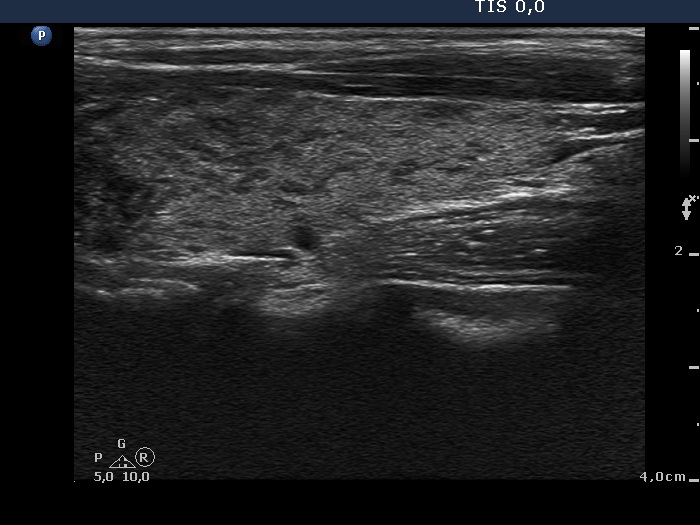

Graves' disease - Case 572

Follow-up investigation 15 months after first visit (ultrasonographic picture 5)

Left lobe, longitudinal scan.